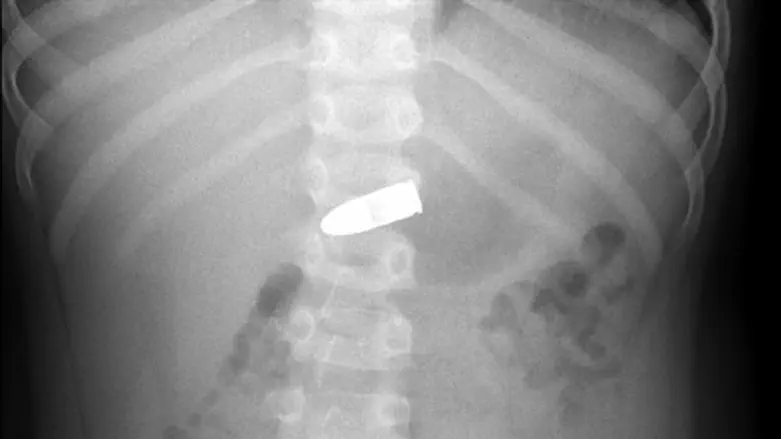

לאחר שבוצע צילום רנטגן בו נמצא הקליע, התייעצו מומחי המחלקה עם צוות המכון לגסטרואנטרולוגיה, מומחים לטוקסיקולוגיה ועם חבלן משטרה.

במרכז שניידר מסבירים כי ככלל, גופים זרים נשלפים בפעולה אנדוסקופית בחדר ניתוח, אך במקרה הזה היה חשש גדול כי מגע המתכות יוביל לתגובה כימית בגופו של הילד. לפיכך הוחלט להמתין שהקליע יצא באופן טבעי מגופו של הילד. כעבור מספר ימים, יצא הקליע מגופו של הילד.